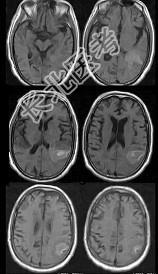

- 单项选择题男,76岁, 突发神志不清,伴呕吐6小时, MRI检查如图所示,最可能的诊断为 ( )

A、出血性脑梗死

B、肿瘤出血

C、原发脑出血

D、脑结核

E、脑脓肿